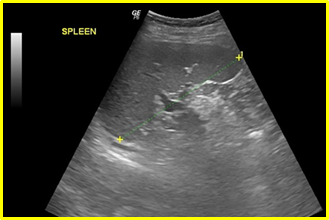

In a 4-years period (from 2016 to 2019) a retrospective study of 887 patients with fatty infiltration of the liver was performed, out of which 608 were males and 272 were females, aged 42 to 69 and 7 obese children (age from 8 to 13 years). All patients were examined in the ultrasound cabinet of our hospital (hospitalized, regular appointments and emergency incidents) and subjected to upper abdominal ultrasound scan, with convex transducer 4C MHz, in three ultrasound imaging planes: transverse, oblique and sagittal planes.5−7 In order to better depict the liver, especially in obese patients or those with excessive intestinal gas, the patients were asked to inhale deeply and hold their breath for the duration of the ultrasonographic examination for a few seconds at a time, so that the liver could be visible in its entirety. The ultrasound examination revealed the echogenicity of the parenchyma of the liver and was compared with the parenchyma of the right kidney, the spleen and the pancreas (Figure 1−3). Τhere is always the risk of missing a diagnosis of mild hepatic steatosis on ultrasound if there is concurrent chronic renal disease, which increases the echogenicity of the kidneys (Figure 4), if there is any doubt that the patient might have a chronic renal disease, comparison of the liver to the left kidney and the spleen may be useful.8

Figure 2 Normal parenchyma of the spleen for comparison.